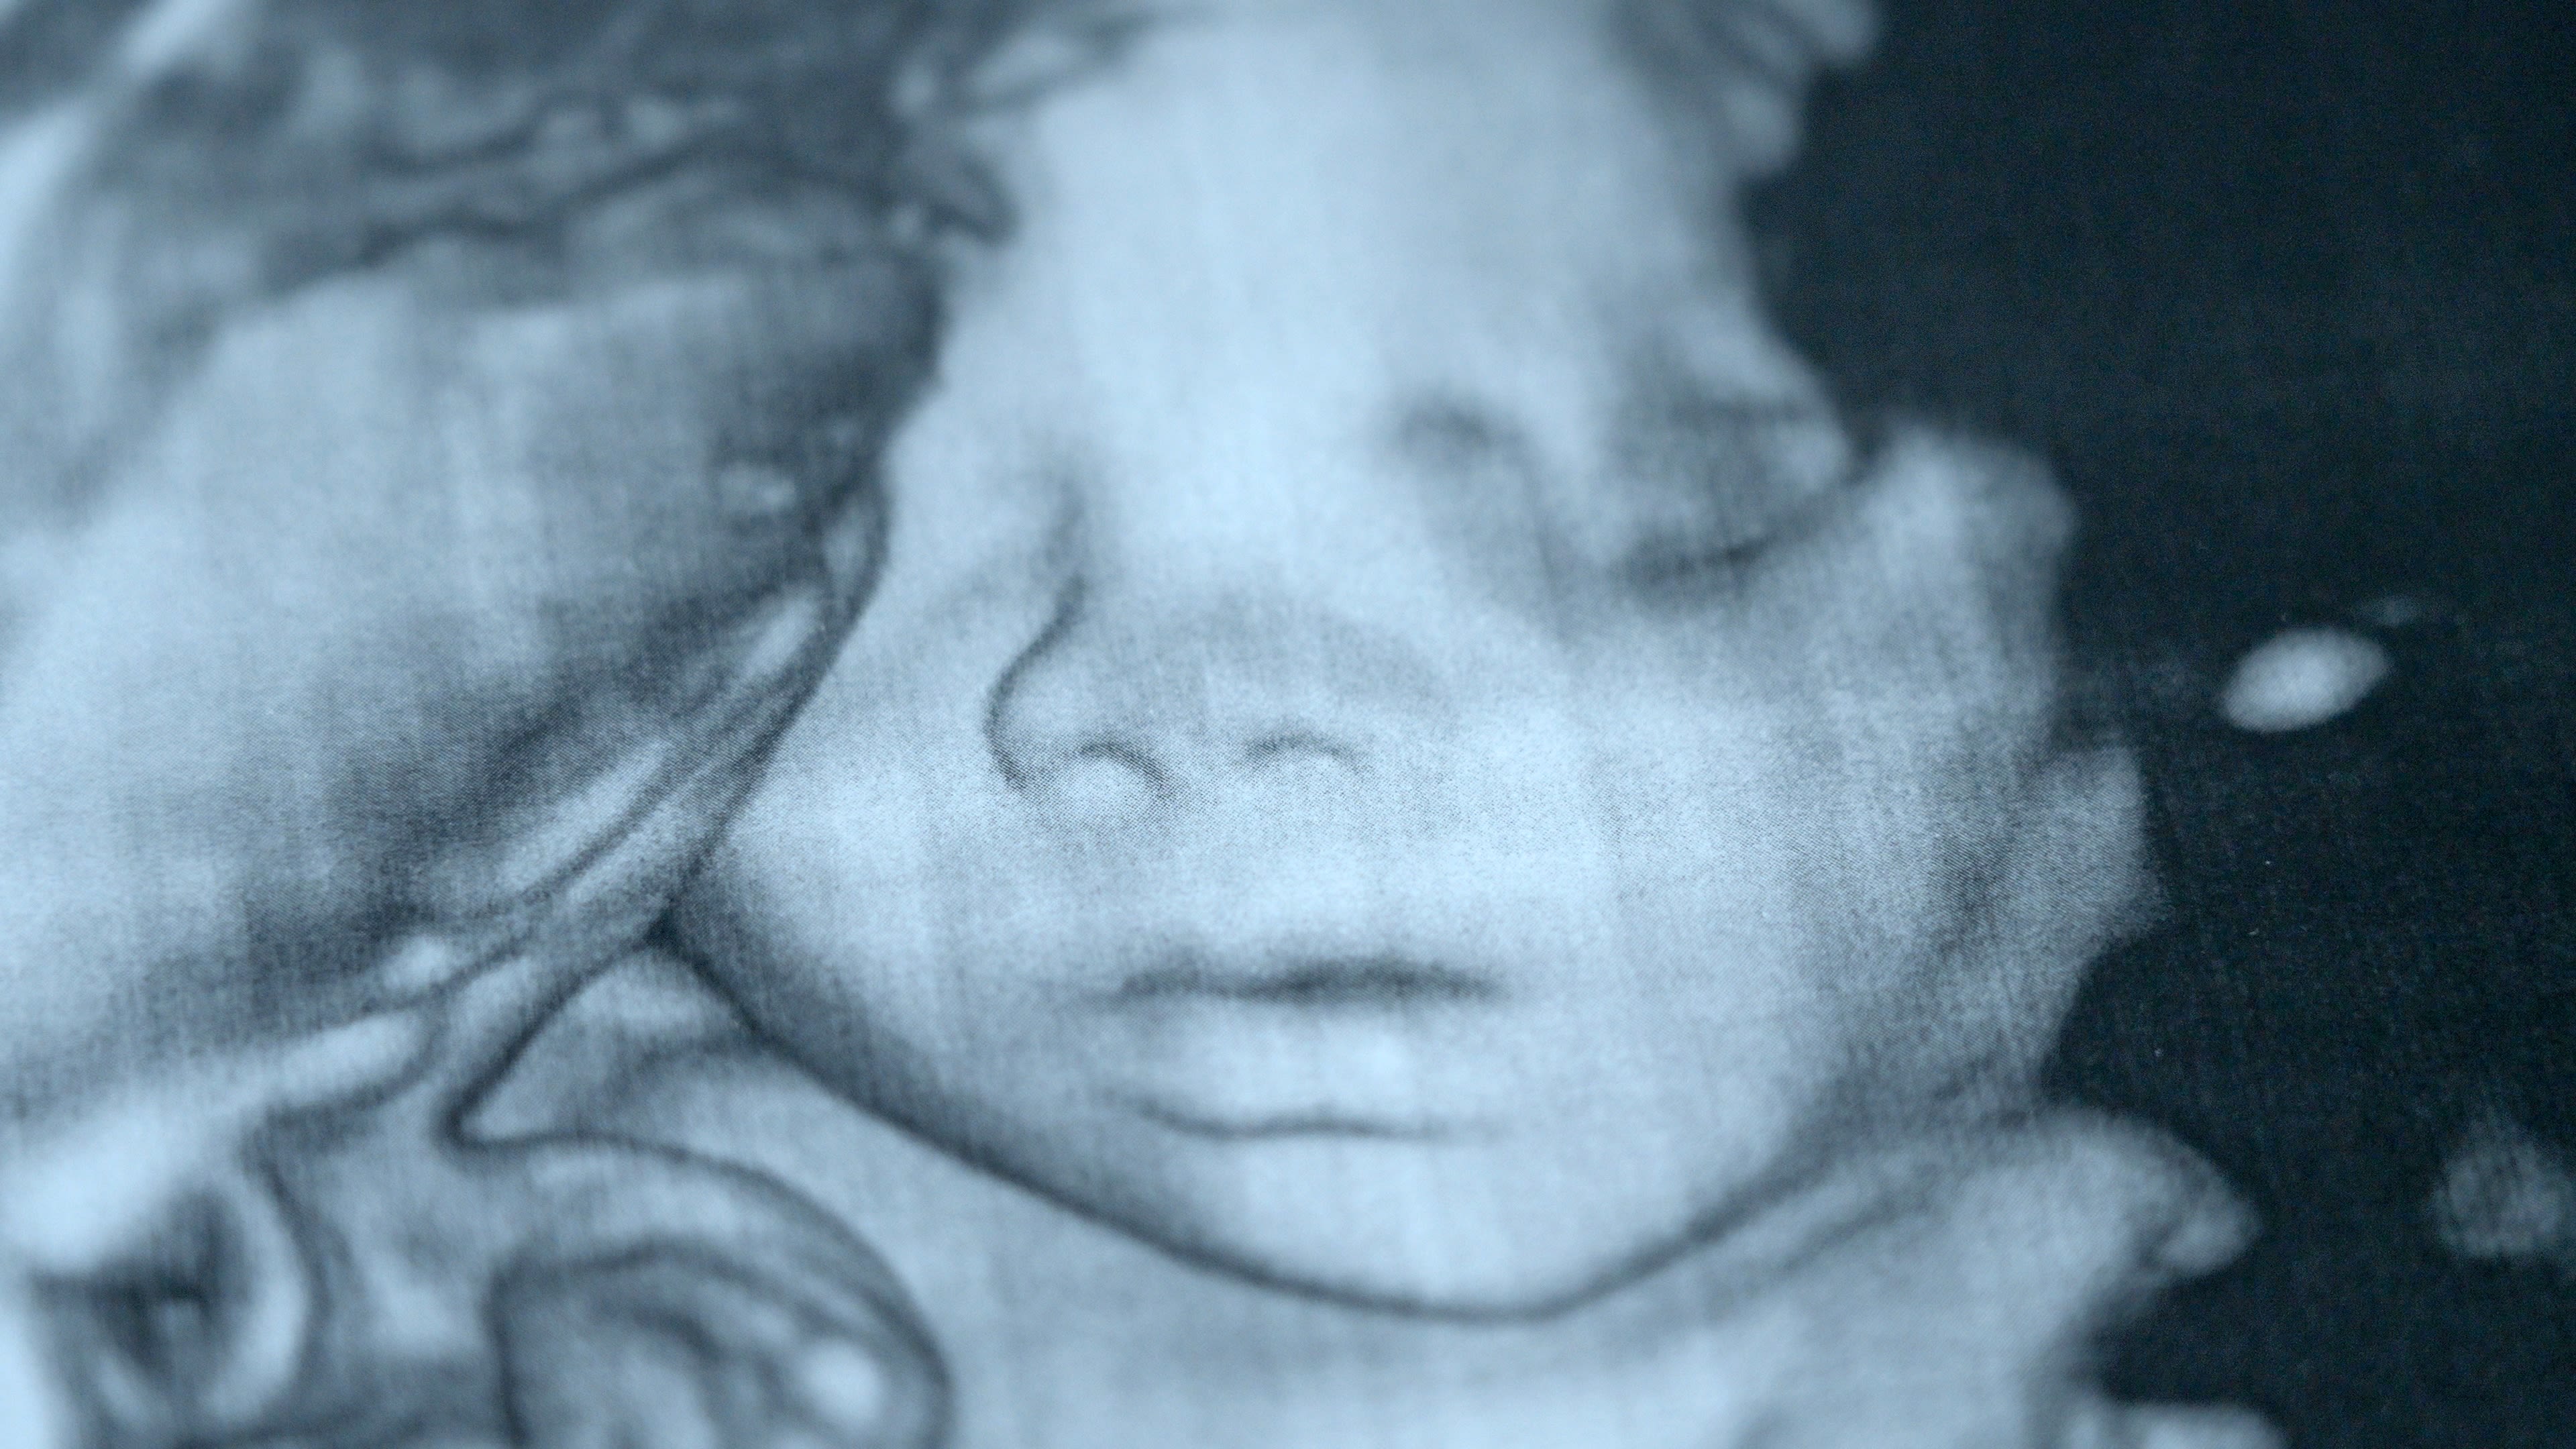

Fue en medio de la pandemia que la ucraniana Viktoria Huzova contrajo matrimonio. Ahora, a sus 28 años, la posibilidad de convertirse en madre está marcada por la invasión a gran escala de Rusia a Ucrania.

“El primer año no hubo pensamientos al respecto. Al contrario, debido al estrés, comencé a tener algunos problemas relacionados con el sistema reproductivo”, contó. Viktoria lo describe como el “síndrome de vida retrasada”, que se manifiesta al desear posponer decisiones o eventos importantes de la vida, hasta que mejoren las circunstancias.

No obstante las dificultades que la invasión rusa impone al pueblo ucraniano, algo cambió en la percepción de vida de ella y de su esposo.

“Entendimos que la guerra podía durar un año, dos años, podía durar diez años. No podemos influir en esto de ninguna manera y no podemos saber cuándo terminará” .

Así que el deseo de este matrimonio de convertirse en padres, fue más potente que las preocupaciones que les produce la guerra.

Viktoria habla con gratitud y esperanza: “La guerra puede continuar durante muchos años más, pero nuestra vida no termina ahí. Seguimos viviendo”.

Clínica Hryshchenko de Medicina Reproductiva

Hospital de Maternidad de Kyiv No. 3